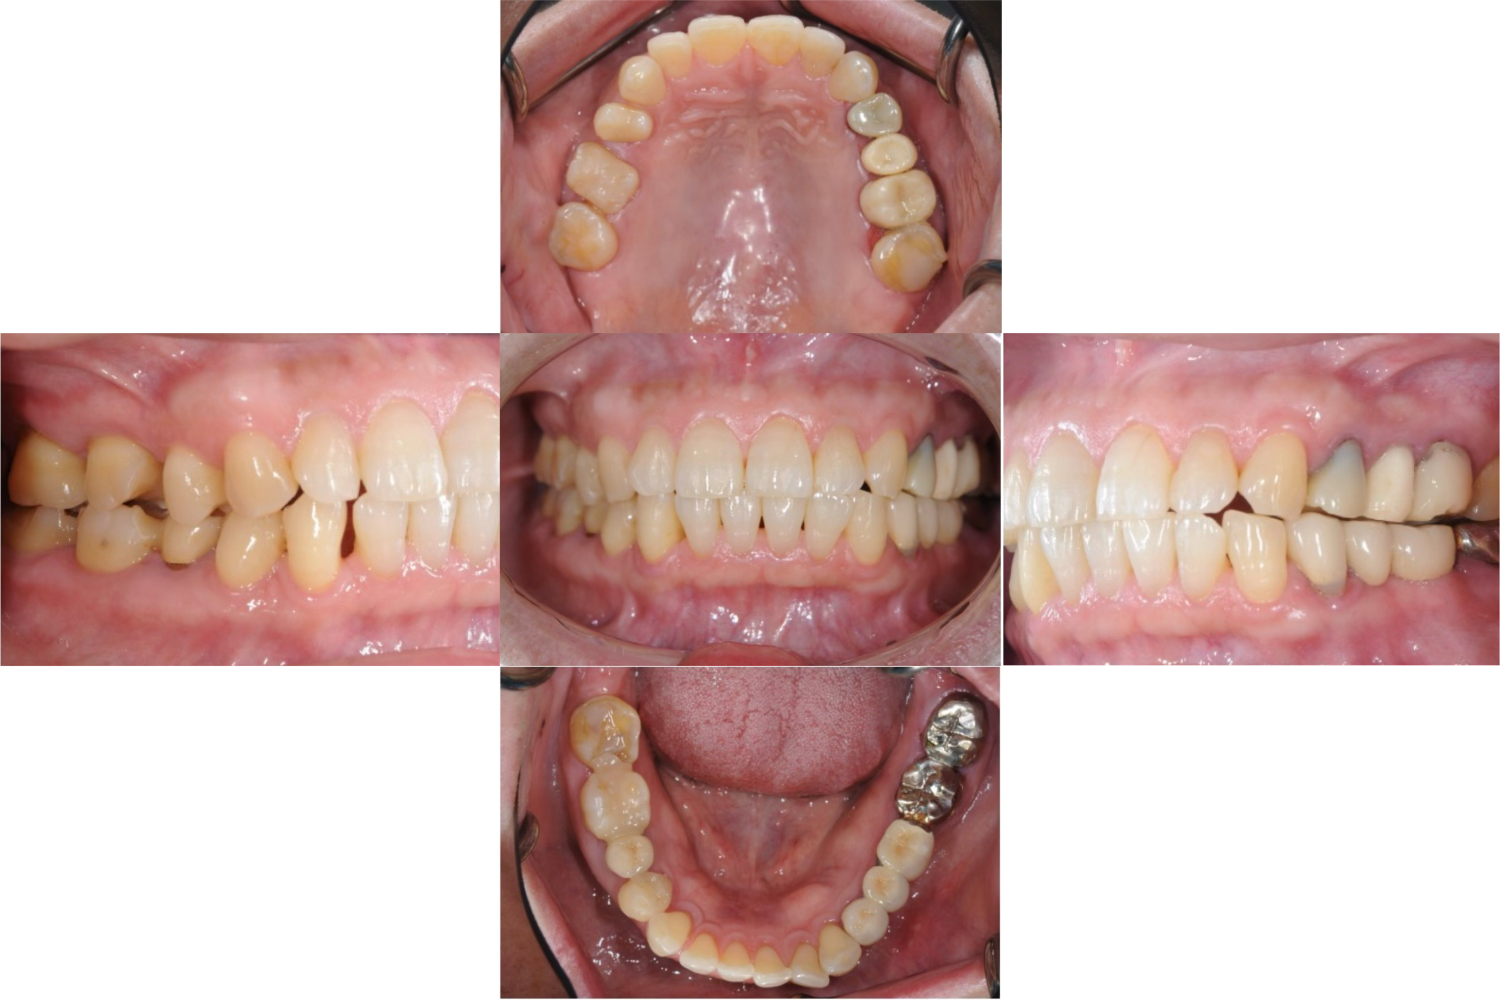

| 主訴 | 全顎治療希望、下の奥の歯が無いので全く噛めない。綺麗で噛めるようになりたい |

| 治療内容 | 下顎臼歯部欠損放置のため、臼歯部においてスペースがないため、全顎治療を行い咬合再構成を行う。 早期においてインプラント治療、咬合関係を模索した後、全顎にわたりセラミックによる補綴治療、その後メインテナンスに移行 |

| 治療費 | 5,410,000円(税込)(インプラントすべて含む) |

| 治療期間 | 1年8ヶ月 |

| 治療回数 | 80回 |

| 想定されたリスク | 食いしばり(パラファンクション)によるセラミックの破折、歯の破折 |